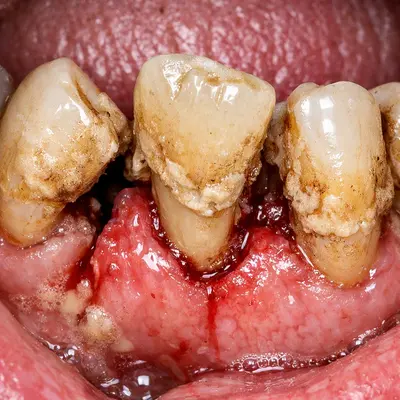

دندان عقل در انتهای دهان قرار دارد و بهخوبی تمیز نمیشود؛ همین موضوع احتمال گیر غذایی، التهاب لثه و عفونتهای مکرر را بالا میبرد. عفونتهای تکرارشونده میتوانند به دردهای مداوم و حتی دردهای مزمن فک منجر شوند.

با گذشت زمان، فشار دندان عقل به دندانهای کناری میتواند باعث آسیب به دندان مجاور، پوسیدگی بیندندانی یا تحلیل استخوان موضعی شود؛ مشکلاتی که درمان آنها ساده نیست.

اگر علائم عفونت یا التهاب وجود دارد، اول آن را جدی بگیرید.

درد ضرباندار، بوی بد دهان، تورم لثه یا ترشح میتواند نشاندهنده التهاب یا عفونت باشد. در چنین شرایطی ممکن است ابتدا کنترل عفونت و سپس جراحی انجام شود تا هم بیحسی بهتر اثر کند و هم تجربه درمان آرامتر شود.